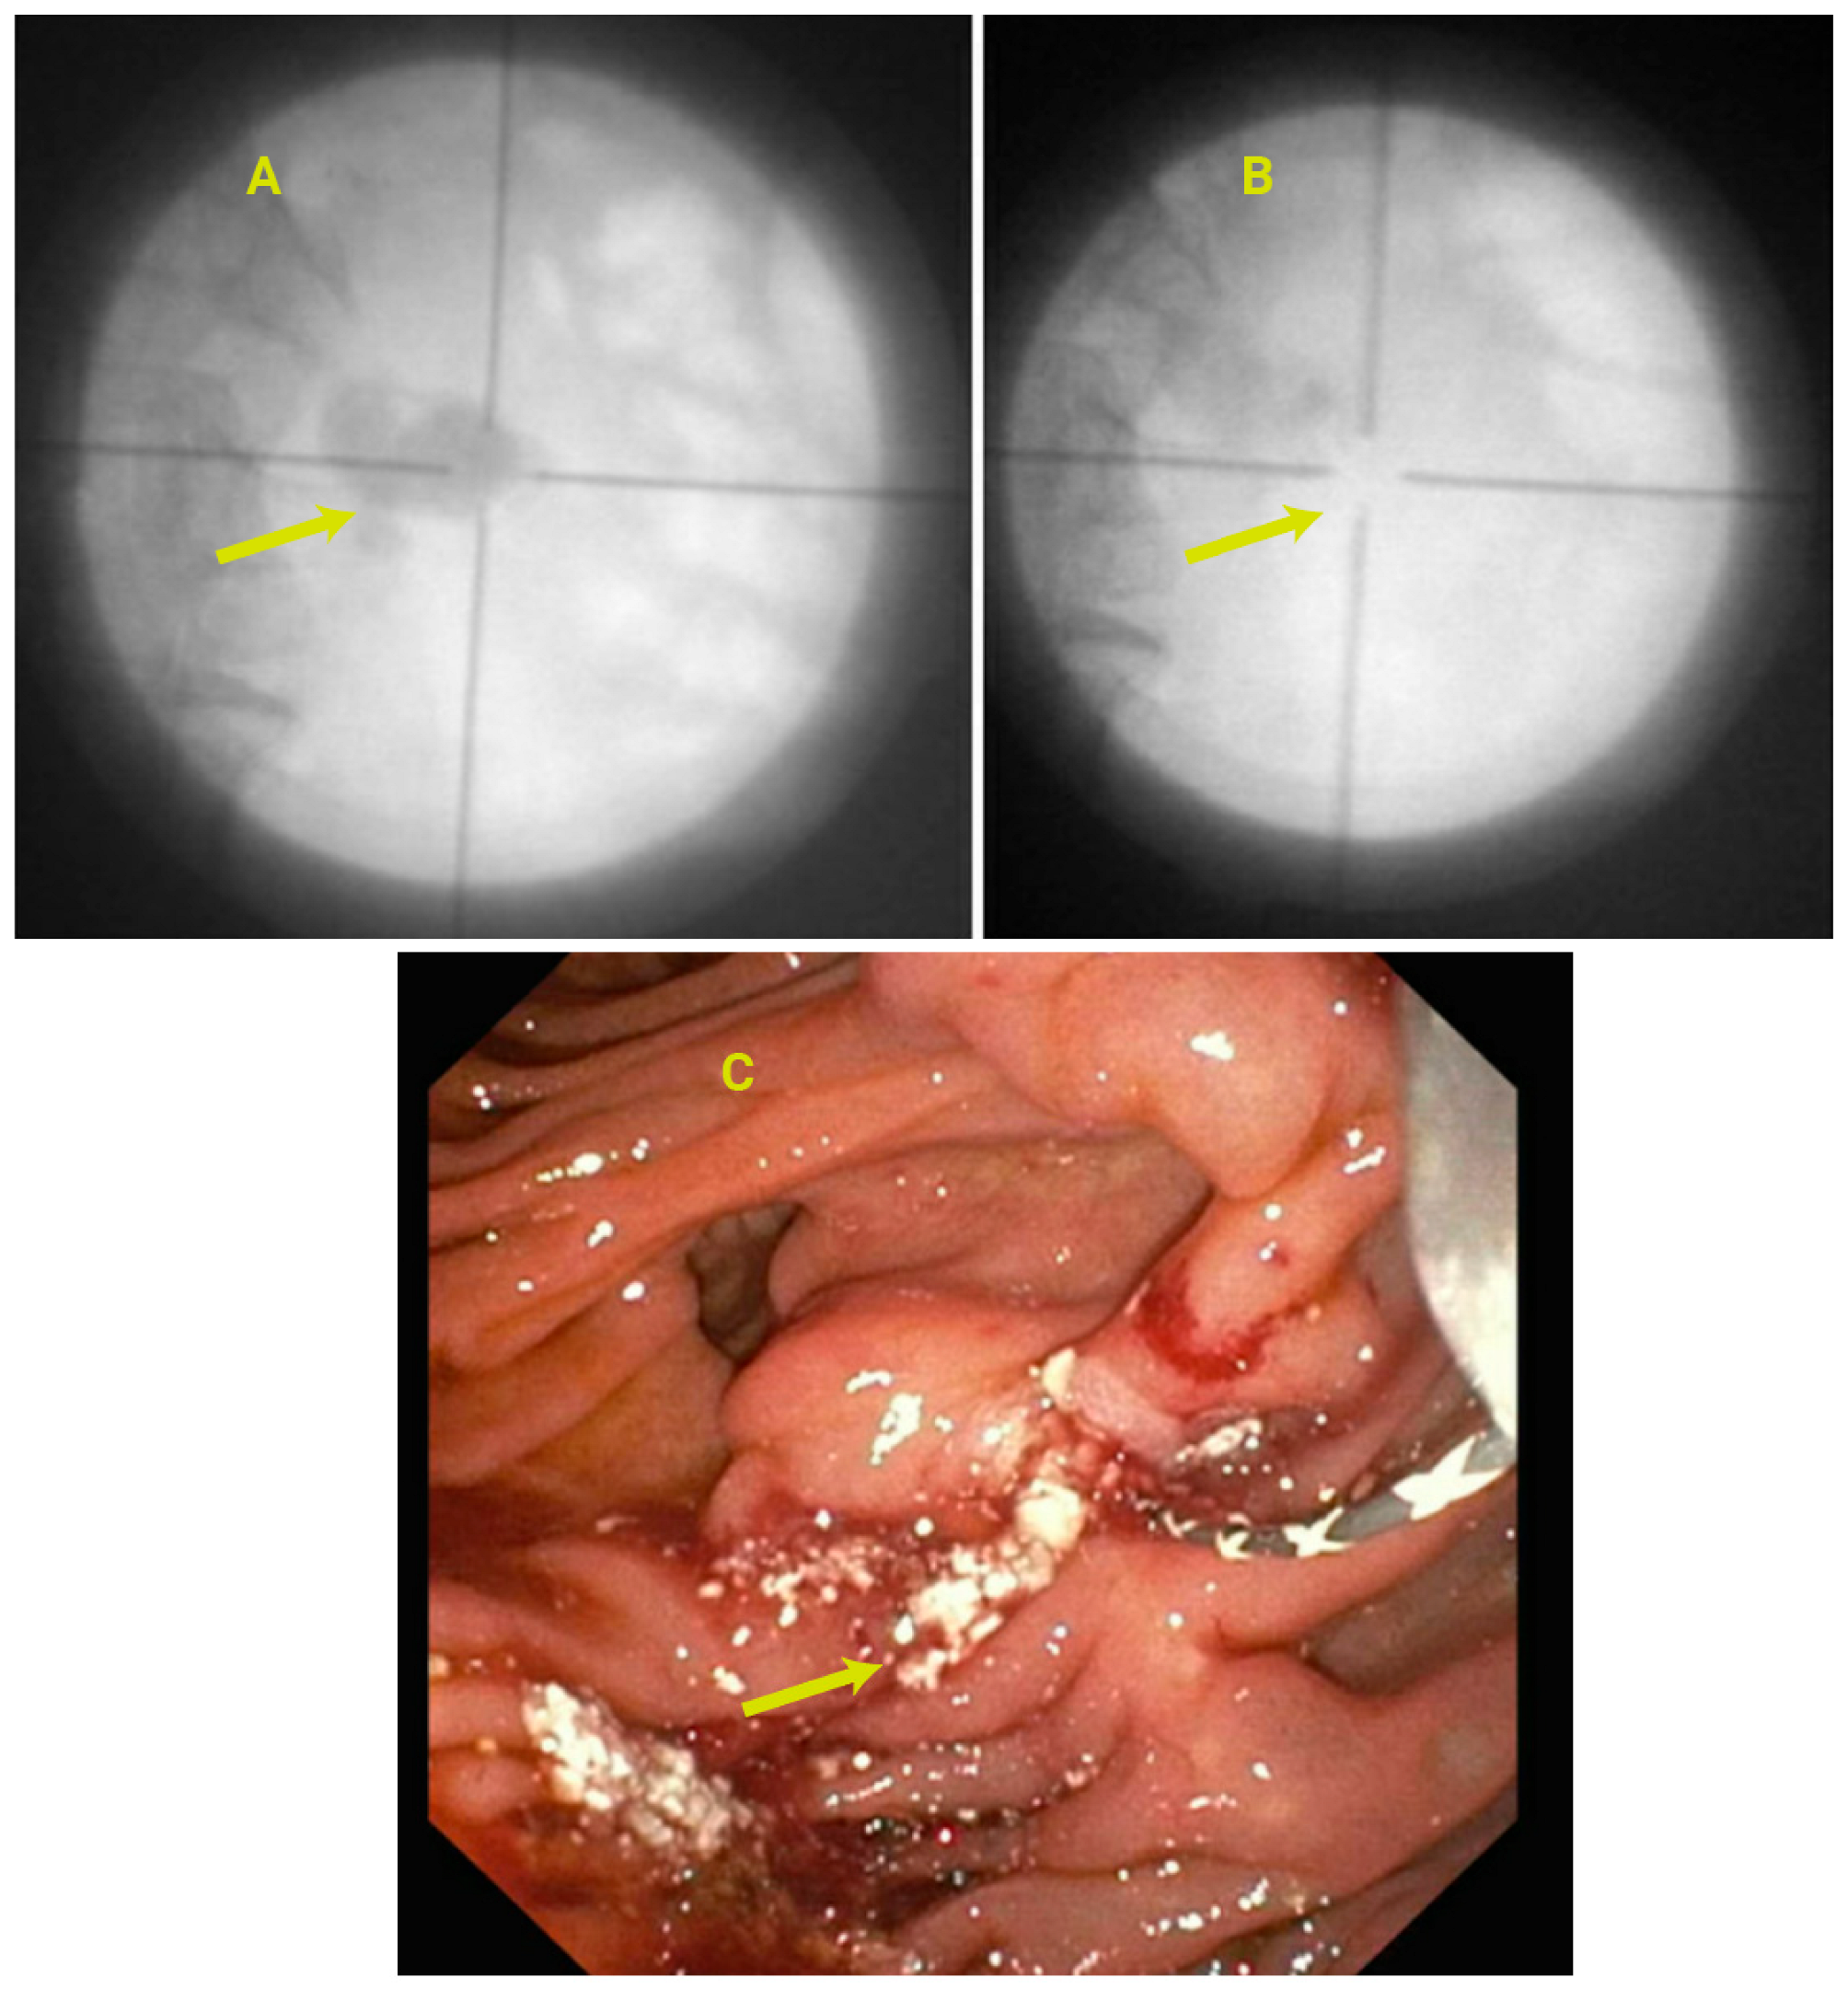

3.15. Endoscopic Management of PD Calculi and Strictures

3.16. Role of EUS in the Management of CP